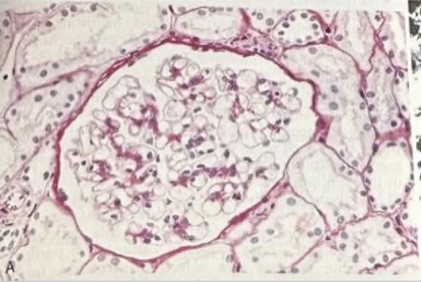

An 8 year old boy is brought to the office due to acute facial puffiness. His mother reports that he has been fatigued and has had dark urine. The patient was treated for a skin infection 3 weeks ago but has no chronic medical conditions. Temperature is 97 F, BP is 140/94. PE shows periorbital edema and mild pitting edema along the ankles. Renal biopsy was performed and the sample is shown below.

The fluorescent areas on the slide most likely indicate the presence of which of the following substances?